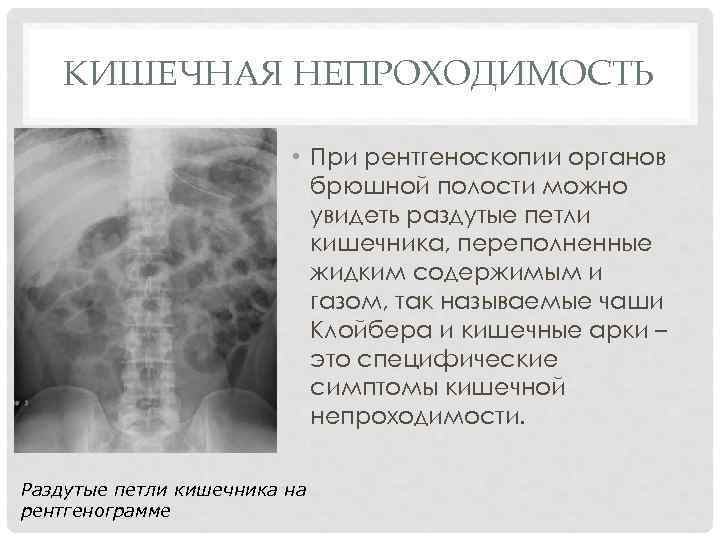

Нормы обзорной рентгенографии брюшной полости